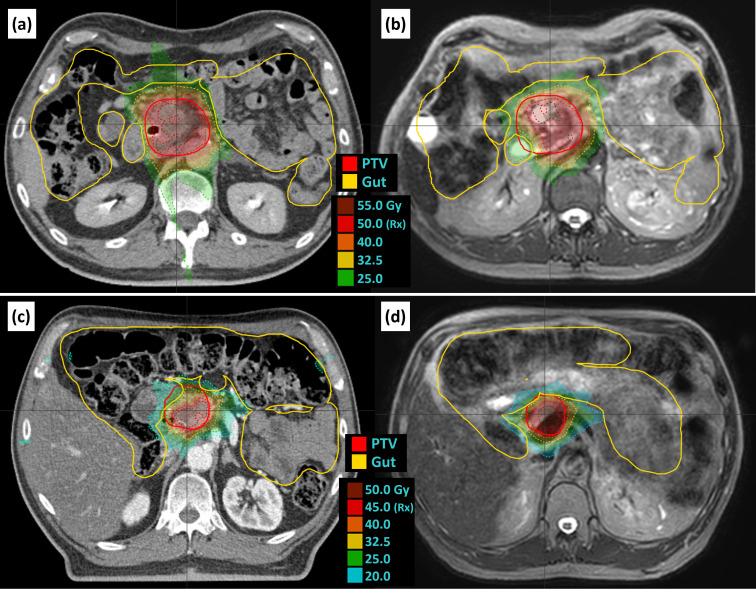

This work presents a method to treat stereotactic body radiation therapy (SBRT) for pancreatic cancer on a magnetic resonance-guided linear accelerator (MR-linac) using daily adaptation, real-time motion monitoring, and abdominal compression.

METHODS

The motion management and treatment planning process involves a magnetic resonance imaging (MRI) simulation with cine and 3D images, a computed tomography (CT) simulation with a breath-hold CT and a 4DCT, pre-treatment verification and planning MRI, and intrafraction MRI cine images.

The results from 26 patients were included in this work. Our motion management process results in consistent motion analysis on the CT simulation, MRI simulation, and each treatment fraction. The liver dome was found to be an overestimate of tumor superior/inferior (SI) motion for most patients. Adding compression reduced SI liver dome motion by 6.2 mm on average. Clinical outcomes are similar to those observed in the literature.

本研究介绍了一种在磁共振引导直线加速器(MR直线加速器)上使用每日适应性调整、实时运动监测和腹部压迫来治疗胰腺癌立体定向体部放射治疗(SBRT)的方法。

运动管理和治疗计划过程包括使用电影成像和三维图像的磁共振成像(MRI)模拟、屏气CT和四维CT的计算机断层扫描(CT)模拟、治疗前验证和计划MRI以及分次治疗期间的MRI电影图像。

本研究纳入了26例患者的结果。我们的运动管理过程在CT模拟、MRI模拟和每次治疗分次中都能实现一致的运动分析。对于大多数患者,发现肝顶对肿瘤上下(SI)运动的估计过高。增加压迫后,肝顶SI运动平均减少6.2毫米。临床结果与文献中观察到的结果相似。